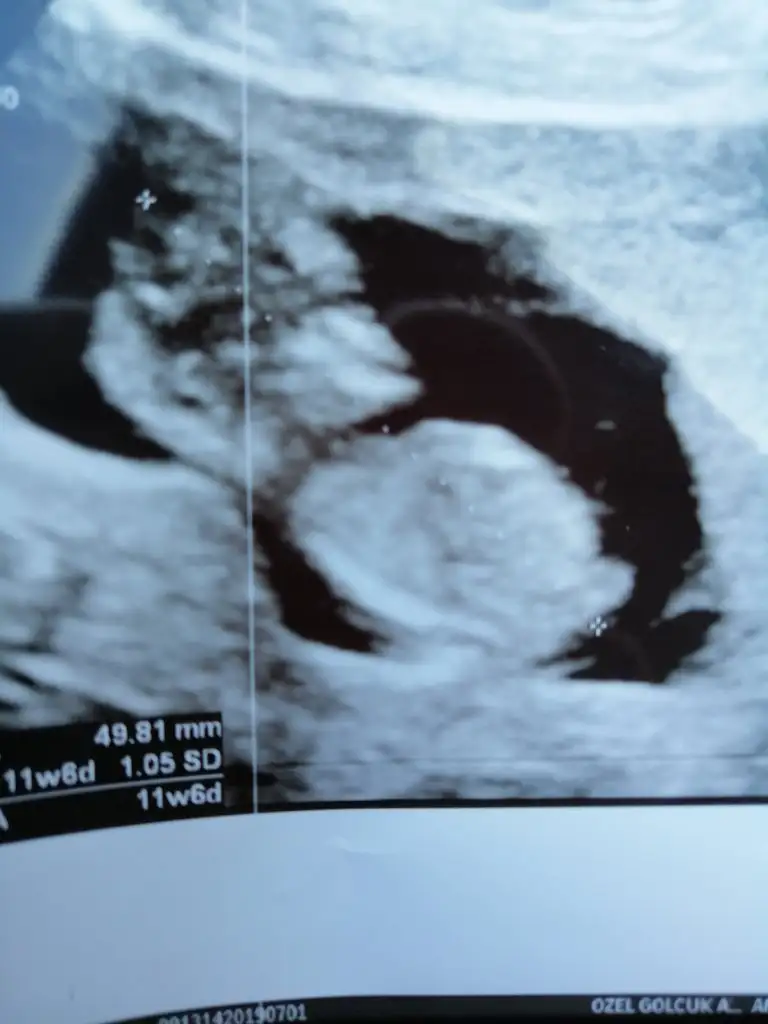

CAnım benım seni okadar iyi anlıyorumki bende o kötü haftadayım biri 11 biri 12 haftada durmuştu okadar korku içindeyım ki hep dua edıyorum seni çok iyi anlıyorum oyuzden bende cuma devlete gıdıcem sırf meraktan memelerımı kasıklarımı kolaçan etmekten yoruldum... inş carsamba guzel haber alıcaksın inanıyorum igne kullanıyormuydun sen